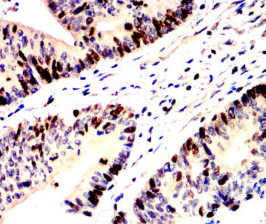

IHC    1/200 - 1/1000